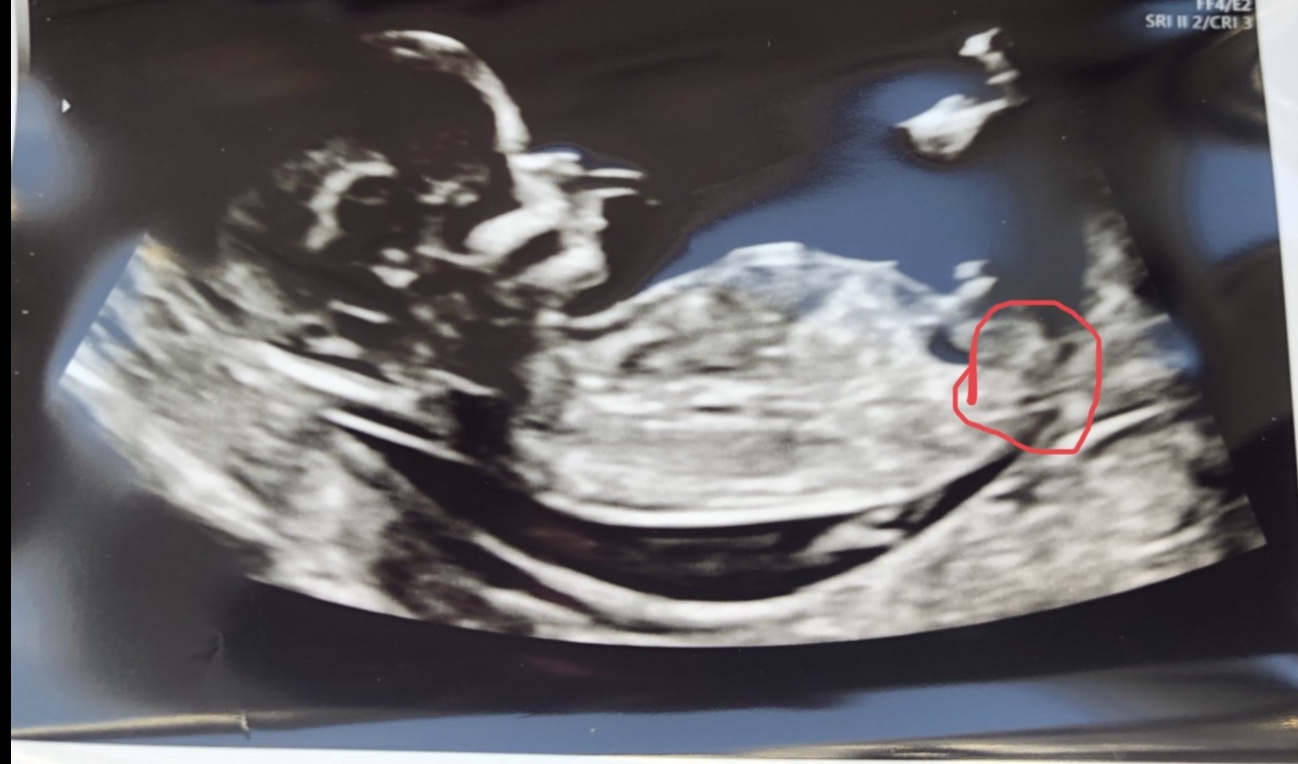

Hi :happy: What do you think: Boy or Girl? Picture is from 13+1 :-)Attachment 41359

Boy 😊